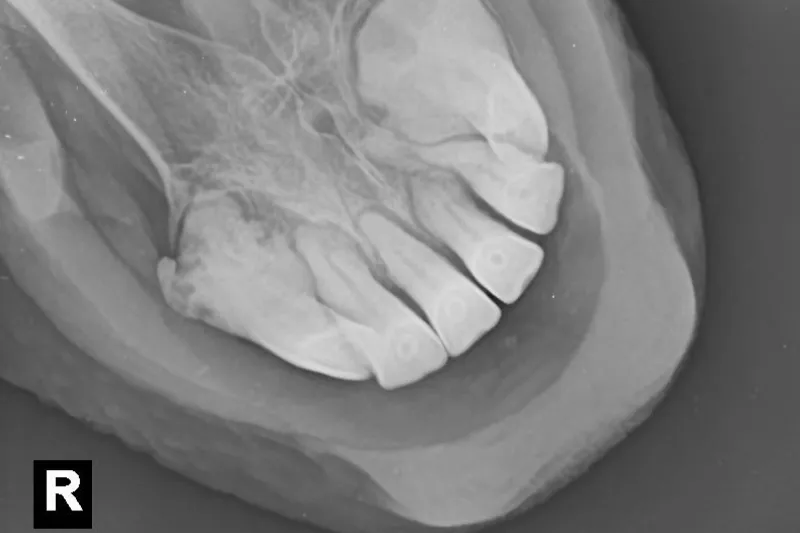

EOTRH is definitively diagnosed on X-rays, usually taken when we see changes to the external appearance of the teeth (gingival recession, swellings over the tooth roots and periodontal disease are commonly associated with the disease) or a change in oral behaviours (difficulty chewing or biting down onto carrots, bad breath, bitting problems, head shaking)¹ EOTRH is a very painful condition due to both the destruction of the normal tooth structure, including potentially the nerve supply to the tooth itself, and also the secondary infection and inflammation.